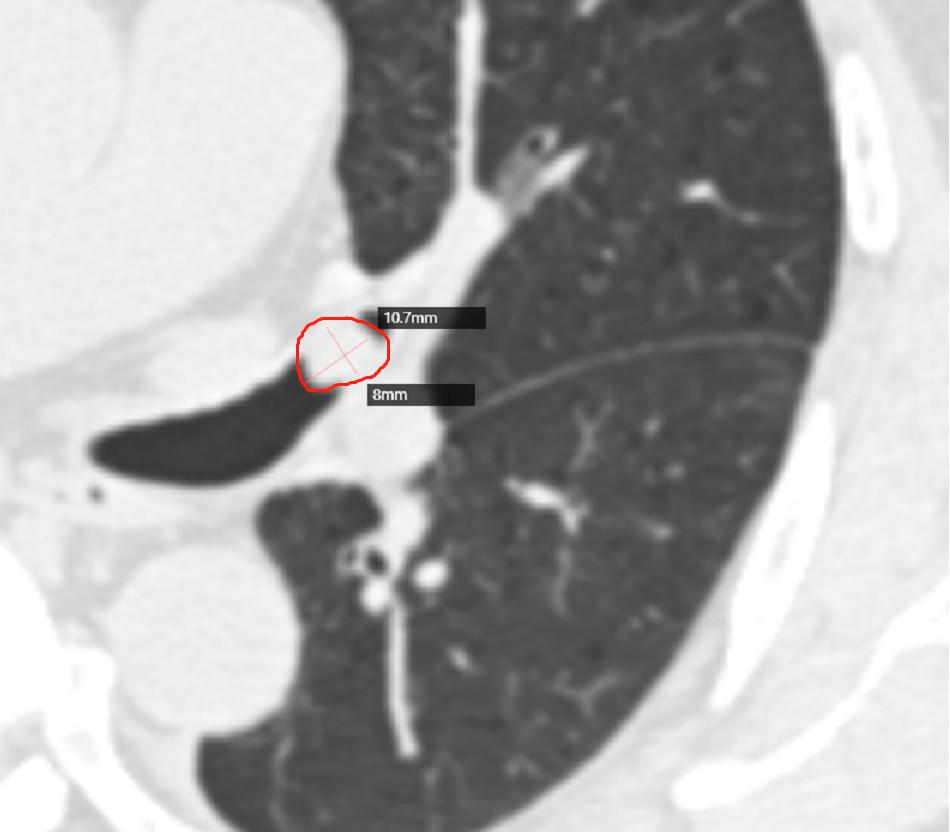

2022年6月20日上班遇到的病例(1):小鳞癌

薛先生 59岁,刺激性咳嗽一周。

左肺上叶主支气管结节,局部管腔狭窄、阻塞

病灶大小约10mm×8mm

多平面重建各方位显示病灶对支气管受压受阻情况

分析:肺鳞癌是来源于支气管上皮的一种恶性上皮性肿瘤,可表现角化和/或细胞间桥特征,约占原发性肺癌的40%-50%。肺鳞癌的大部分是中央型肺癌,病灶大分部起源于较大的支气管,这个影像学在早期,如果不仔细很难发现,或者说 早期极其难发现 。我们通常见到的肺鳞癌都是病灶或者肿块比较大的时候才能发现。大部分人是在出现不间断的刺激性咳嗽时做胸部CT发现。